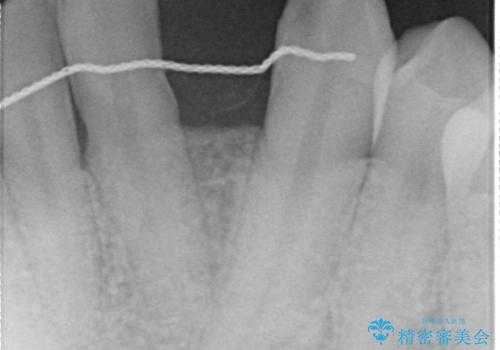

左下123番のブリッジになるが、左下1番と3番の歯軸が合っておらず神経治療が必要になる可能性があるため部分矯正を提案したところ、希望されなかったため、そのままの歯軸でオールセラミッククラウンによる補綴を行いました。

- 根管治療により痛みや腫れがひかない事や、術後に痛みや腫れが生じる事、治療によるファイル破折やパーフォレーションなどの偶発症、術後の歯根破折を生じる可能性もあります